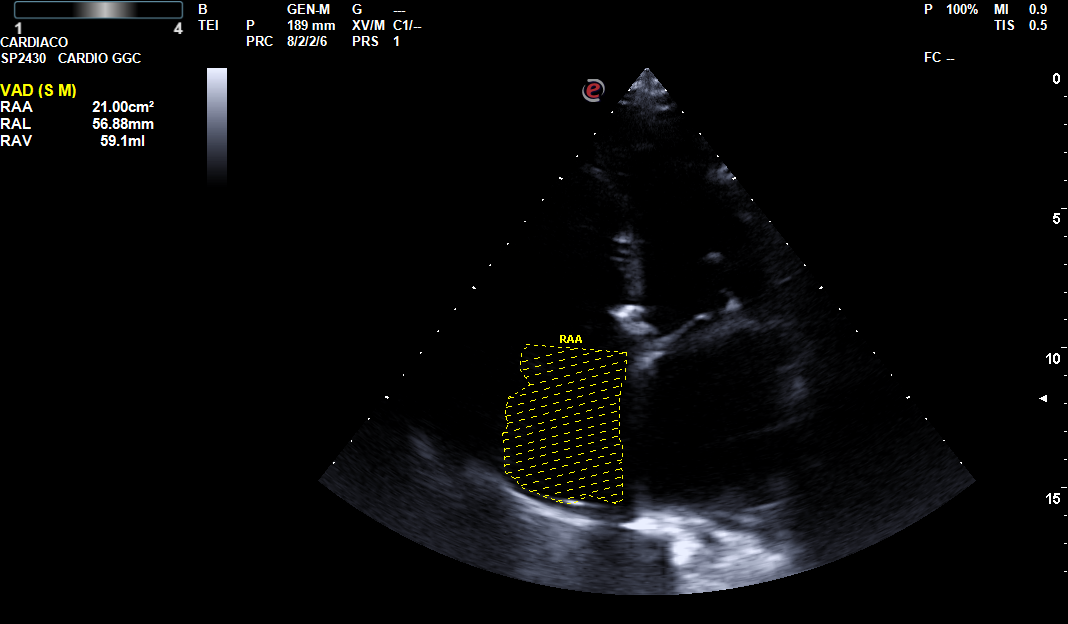

A través de una serie de casos clínicos surgidos tanto en la consulta como en los domicilios, hemos llevado a cabo una revisión de cómo aplicar la ecografía clínica para mejorar el diagnóstico diferencial del paciente con disnea y su posterior seguimiento. Tras la realización de dicha revisión bibliográfica nos reunimos los responsables de ecografía del centro de salud para realizar una serie de sesiones clínica y compartir nuestra experiencia y plantear un algoritmo sencillo de aplicar en nuestra práctica diaria.

La disnea es una sensación subjetiva de dificultad para respirar siendo común a múltiples situaciones clínicas de elevada prevalencia. Las causas más frecuentes, las de origen respiratorio y las de causa cardiaca, incluso comparten factores de riesgo, por lo que en ocasiones coinciden en el mismo paciente. En estas circunstancias no resulta sencillo solo por la clínica intuir cual puede ser el origen de la disnea. La ecografía multiórgano, constituye una herramienta muy útil para determinar o descartar el origen cardiaco de la disnea. Siendo imprescindible en los pacientes inmovilizados, en los que los ecógrafos ultraportables nos ha aportado un nuevo manejo de la disnea en el paciente domiciliario.

La ecografía multiórgano junto con la mejora de la portabilidad de los ecógrafos nos permiten hacer un diagnóstico más certero del paciente que consulta por disnea tanto en el centro de salud como en su domicilio.